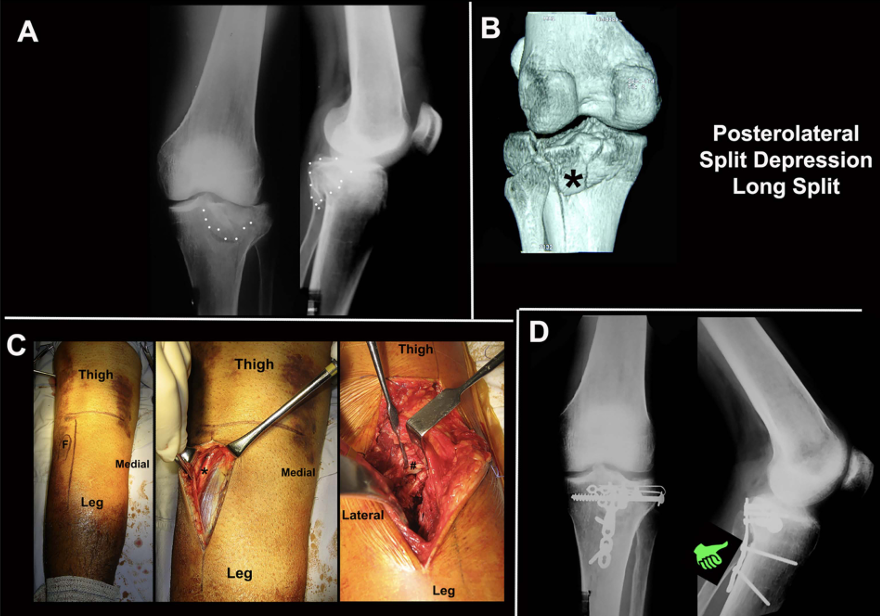

病例展示:后外侧劈裂塌陷骨折(Kfuri-Schatzker type II P型),A. 入院X线片,B. CT三维重建:清晰显示一个延长的后外侧劈裂骨块(星号标注)。此形态学分类有助于理解骨折的稳定性和手术策略。C. Carlson入路手术步骤:患者俯卧位,切口略偏内侧,与腓骨走向平行。神经显露:腓总神经(星号标注)位于浅筋膜下方、腓肠肌外侧头外侧,易于辨识。深层显露:将比目鱼肌从腓骨上剥离并抬起。将腘肌向内侧牵开。此时可显露外侧半月板(#号标注)。关节内观察:将外侧半月板向近端牵开后,可见后外侧缘的粉碎情况。